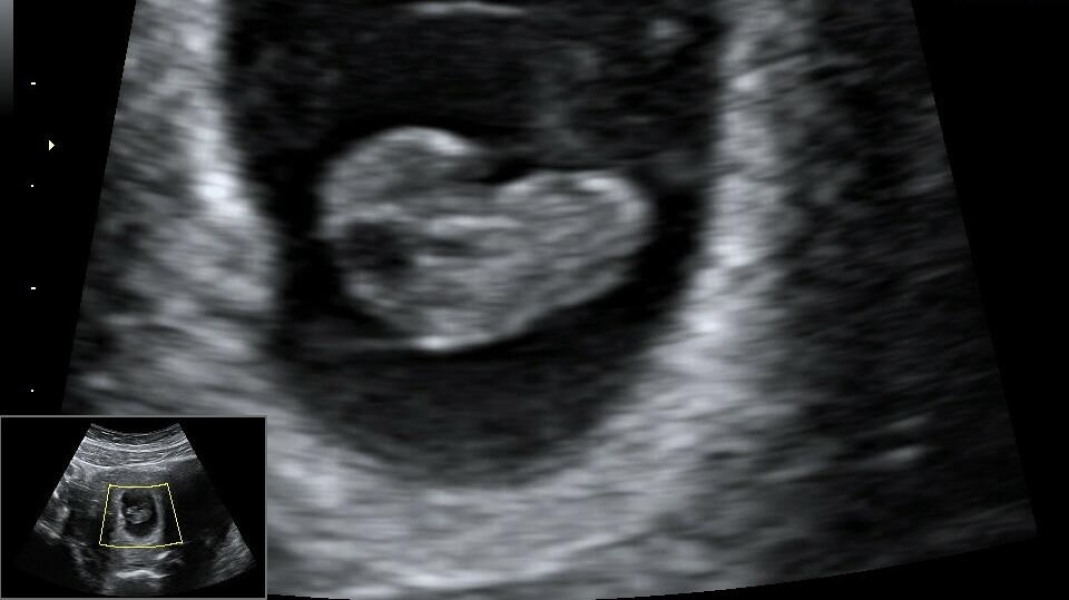

Stupid question ladies. Had my early scan.. which one of these things is the baby? I didn't really get seeing it on the monitor as they really struggled to get a good image as it was very blurry. The look kinda similar to me and this is my first pregnancy so I can't really tell what is what and they never really pointed it out.

@ChildOfTheMoon the right lower arrow is the uterus and embryo.

(Radiographer)